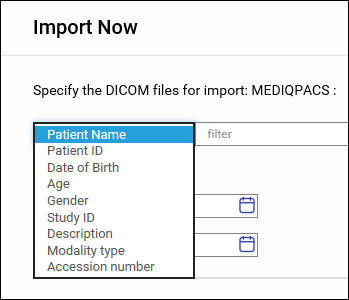

用户可按计划将 DICOM 图像导入到基于 NAS 的 PACS 服务器,也可以将它们直接导入。

自动导入图像

手动导入图像